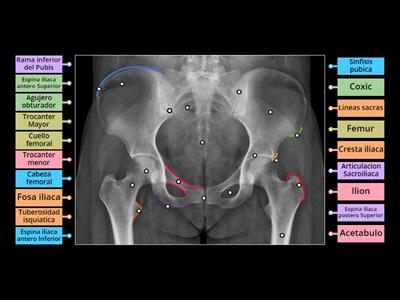

Anatomia Rx de Pelvis

Označený diagram